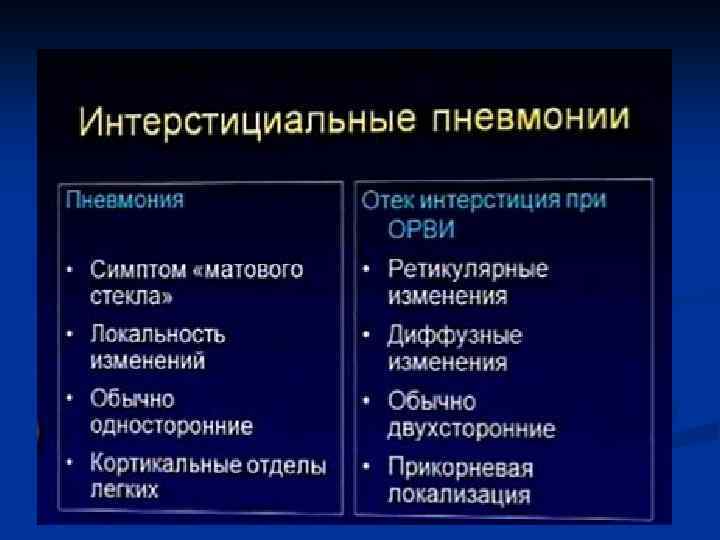

Интерстициальная пневмония

Интерстициальная пневмония n n n n Хуже диагностируются чем паренхиматозные Чаще – постгриппозные Вяло текут ОАК – почти норма Субфебрилитет Жалобы на недомогание, сухой кашель, вялость Это продуктивное воспаление (лечится тяжело)

Интерстициальная пневмония n n Характеризуется воспалительной инфильтрацией интерстиция Вызывающие ее микроорганизмы: вирусы, микоплазма, рикетсии, приводят к отеку и лимфацитарной инфильтрации стенок бронхов, Далее распространяется по междольковым перегородкам. Лимфоцитарная инфильтрация перибронхиальных альвеол, что придает сходство с очаговой ПН

Интерстициальная ПН - ретикулярные = сетчатые изменения легочного рисунка - преимущественно центральным = прикорневым распределением - могут быть очаговые сливающиеся уплотнения легочной ткани

КТ-семиотика интерстициальной пневмонии n n n Понижение прозрачности легочной паренхимы по типу «матового стекла» Утолщение внутридолькового интерстиция Утолщение междолькового интерстиция Утолщение перибронховаскулярного интерстиция Тракционные бронхо- и бронхиолоэктазы Изменения по типу «сотового легкого»